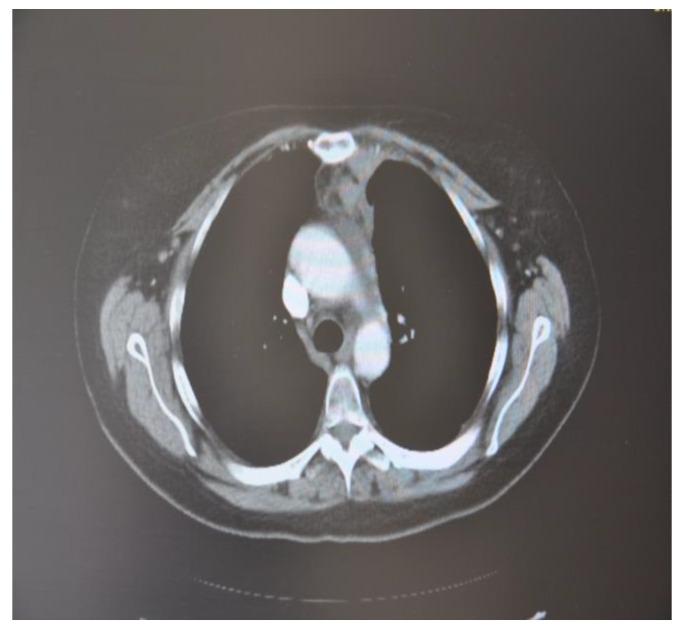

As less invasive options for surgical tumor removal, minimally invasive ablative techniques have gained popularity. Several solid tumors are being treated with cryoablation, a non-heat-based ablation technique. Cryoablation data in comparison over time demonstrates better tumor response and faster recovery. Combining cryosurgery with other cancer therapies has been explored to improve the cancer-killing process. Cryoablation with the combination of immunotherapy, results in a robust and efficient attack on the cancer cells. This article focuses on investigating the ability of cryosurgery to create a strong antitumor response when combined with immunologic agents resulting in a synergetic effect. To achieve this objective, we combined cryosurgery with immunotherapy using Nivolumab and lpilimumab. Five clinical cases of lymph node, lung cancer, bone, and lung metastasis were followed and analyzed. In this series of patients, percutaneous cryoablation and addressing immunity agents were technically feasible. In the follow-ups, there appeared to be no radiological evidence of new tumor development.

作为手术肿瘤切除的微创选择,微创消融技术已经越来越受欢迎。几种实体肿瘤正在接受冷冻消融治疗,这是一种非热消融技术。随着时间的推移,冷冻消融的数据显示出更好的肿瘤反应和更快的恢复。冷冻手术与其他癌症治疗方法的结合已被探索用于改善癌症杀伤过程。冷冻消融联合免疫疗法可以有效地攻击癌细胞。本文重点研究了冷冻手术与免疫药物联合使用时对肿瘤产生强烈抗肿瘤反应的能力,从而产生协同作用。为了实现这一目标,我们使用 Nivolumab 和 ipilimumab 将冷冻手术与免疫疗法相结合。对 5 例淋巴结、肺癌、骨和肺转移的临床病例进行了随访和分析。在这一系列患者中,经皮冷冻消融和免疫治疗具有技术可行性。在随访中,似乎没有新的肿瘤发展的放射学证据。